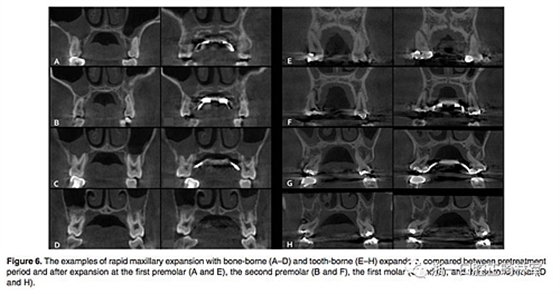

(1)牙支持式和骨支持式快擴之間的比較(Figure 6,Table 1)

骨骼變化:腭中縫線在兩組中都以三角形模式被成功打開,鼻底增加最少,硬腭以下5mm平面出被打開最多(P<0.001)。骨骼的擴張比牙齒的水平要少。除了第一前磨牙區(qū)域的線性測量值外,骨支持式組顯示擴張程度比牙支持式組顯著增加。

牙性變化:兩組的牙槽骨和牙長軸的角度變化都很明顯。牙支持式組在全部區(qū)域都顯示出比骨支持式組更大的頰側傾斜(P<0.01)。牙支持式組的牙槽骨頰傾更明顯,第二磨牙區(qū)域除外(P <0.05)。在第一前磨牙和第一磨牙,兩組在根尖處的橫向距離增加是相似的。然而,在第二前磨牙和第二磨牙中,牙支持式組發(fā)生根尖橫向距離增加較少。在牙冠水平,僅在第二前磨牙處,兩組之間的擴張相似。牙支持式組在第一前磨牙和第一磨牙產生更多的牙冠之間橫向距離增加,而骨支持式更多發(fā)生在第二磨牙。在第一前磨牙和第一磨牙的垂直向變化方面,兩組之間沒有區(qū)別。 第二前磨牙區(qū)頰尖頰傾和腭尖掛下在牙支持式組比骨支持式組更明顯(P <0.05)。在第二磨牙區(qū)域,僅在頰尖頰傾方面兩組有統計學差異(P <0.05)。除了第一前磨牙在牙支持式組的頰側骨開裂明顯(P <0.01)之外,兩組間垂直牙槽骨損失量沒有顯著差異。